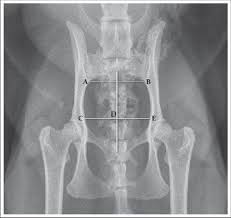

Thirty nine patients with abnormal pelvis were compared with ct and ultrasounds. This provides an excellent look at the large and small bowel. Über 7 millionen englischsprachige bücher. The musculoskeletal system is responsible for form, support, stability and movement. This is a higher quality study than a standard ct. Tanksi and jordan ruby the rich vascular supply of the pelvis not only supports the structures contained within it, including the bladder, rectum, and reproductive organs, but also extends to the lower extremities. Mri of the female pelvis: Ascending colon superior mesenteric vein superior mesenteric artery gonadal vessels linea semilunaris abdominal aorta linea alba inferior vena cava inferior mesenteric artery infe. Anatomy ct axial abdomen and pelvis male male abdomen and pelvis ct scan form no 1. Two radiographic views of the cat's pelvis are used to confirm the diagnosis of pelvic fractures and may also show sacroiliac luxation (dislocation), coxofemoral luxation, or femoral fracture if they are present. 6.1a, b) is a bony ring consisting of paired innominate bones, the sacrum and coccyx. These radiographs of animal anatomy are under the copyright of imaios and can not be freely used. Page 1 of 15 (wow) bony pelvis anatomy skeletally radiographs ct protocols pelvic ring fx sacrum

Anatomy by dr muhammad bin zulfiqar; The bony pelvic girdle consists of the innominate bones bilaterally, and the sacrum and coccyx posteriorly. The innominate bones articulate with each other anteriorly and with the sacrum posteriorly. The following slides are from wikiradiography (wetpaint) here. The pelvic girdle (hip girdle) is formed by a single bone, the hip bone or coxal bone (coxal = hip), which serves as the attachment point for each lower limb.

Anatomy of the pelvis bony anatomy. Posted by radiologypics ⋅ march 21, 2013 ⋅ 1 comment. A ct scan of this area may be done to look for abscesses, tumors, kidney stones, infections, or the cause of unexplained abdominal pain. Its action is the compression of the abdomen. Über 4.500 baumaschinen sofort verfügbar. Ct mri radiographs anatomic diagrams and nuclear images. Tanksi and jordan ruby the rich vascular supply of the pelvis not only supports the structures contained within it, including the bladder, rectum, and reproductive organs, but also extends to the lower extremities. Read the first two articles, small animal thoracic radiography (september/october 2011) and small animal abdominal radiography (november/december 2011), at todaysveterinarypractice.com.